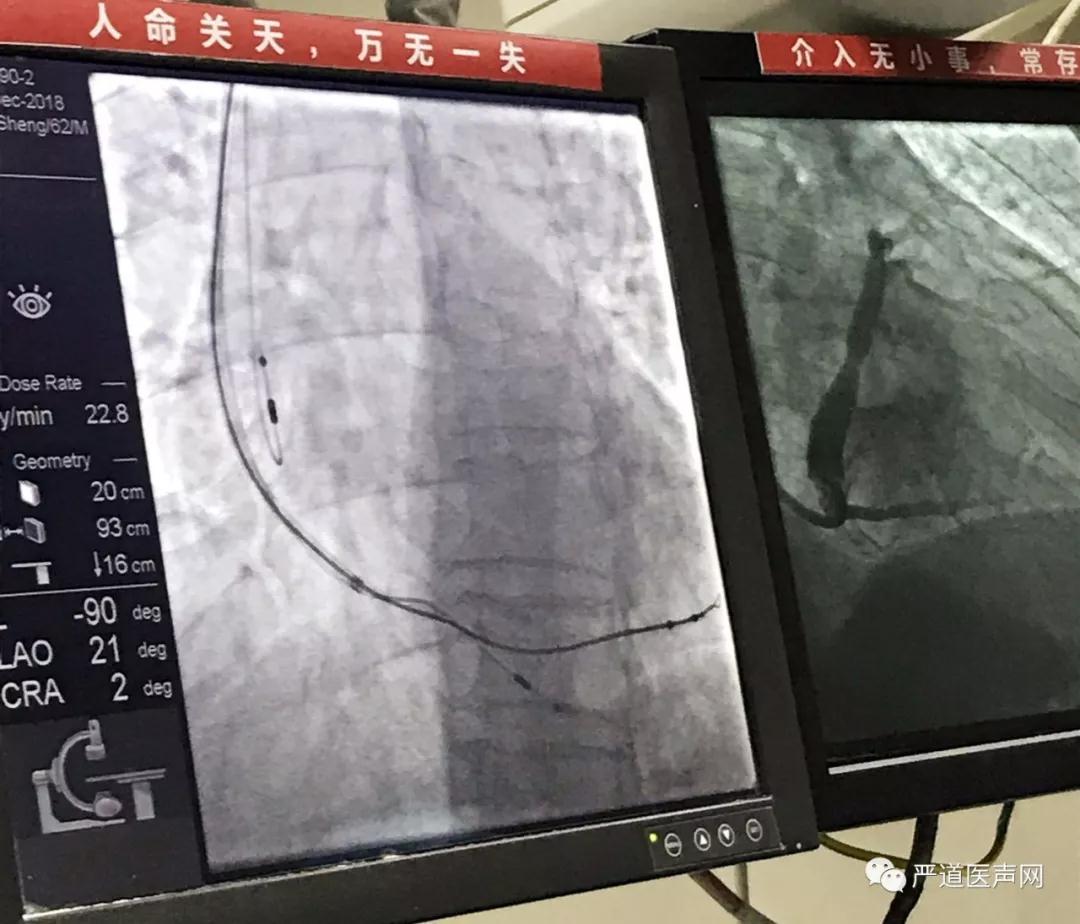

2018年12月19日-21日,洪李锋教授带领武汉市第五医院心内科团队,连续三天为三名心衰患者及一名室速患者植入CRT和ICD。继该中心在2018年第二批次心衰中心通过认证后,持续发力,让完左合并心衰患者悸动的心不再迷茫。

心脏性猝死的预防,一直是全球心内科医生所面临的重大难题,也是我国心血管病患者死亡的主要原因。而绝大多数心脏性猝死由室颤引起,及时有效地除颤,是预防心脏性猝死的关键。ICD是在心脏性猝死预防领域的首选。

心衰治疗,慢性心力衰竭(心衰)是各类心脏疾病的终末阶段,是心血管领域最后的主战场。心脏再同步治疗(CRT)通过恢复左室内部收缩同步性,使室间隔与左室游离壁同步球形收缩;通过AV间期优化恢复房室间同步性,获得最佳舒张期充盈;通过VV 间期优化恢复心室间同步性,获得最佳心室收缩功能。